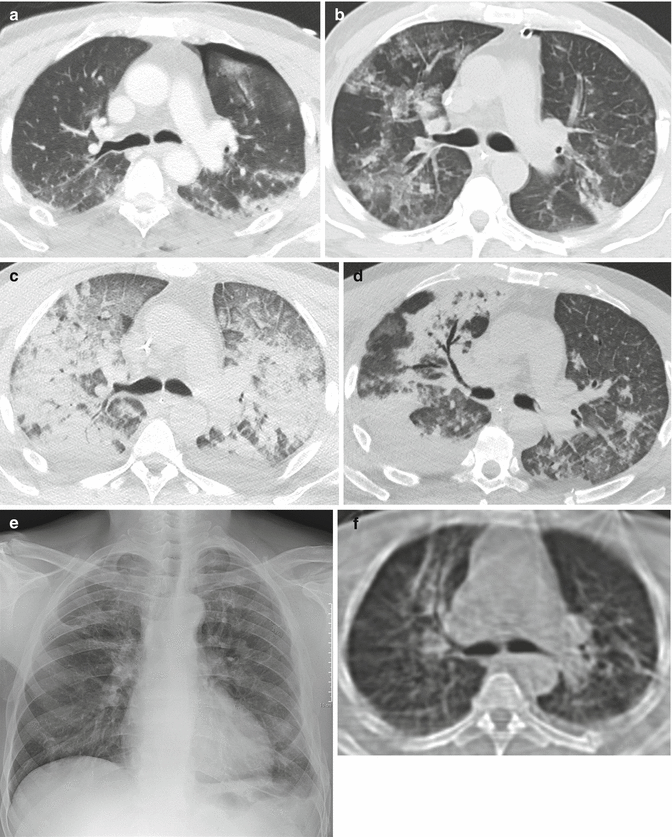

18+ Early Ards X Ray Images. Why some people develop ards and others do not is still unknown. Acute respiratory distress syndrome (ards).

سندرم دیسترس تنفسی حاد ards. It is also the oldest and most common form of imaging. Icu nurses course 2004 tim smith. Why does renal failure occur with ards?